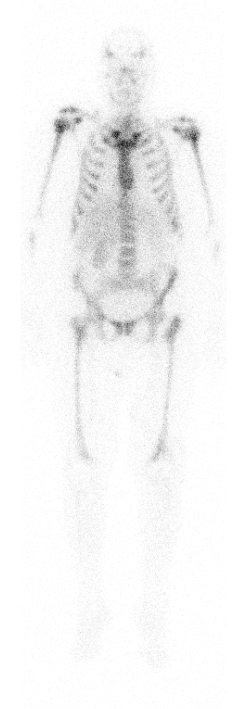

Entzündungsszintigraphie

Hierbei werden spezielle Zellen markiert, die bei Entzündungen gehäuft auftreten (z. B. Granulozyten). Diese können dann dargestellt werden bspw. wenn die Entzündungsursache nicht klar ist. Für viele Fragestellungen bzgl. Entzündungssuche ist jedoch die FDG-PET/CT die genauere Untersuchung, wir informieren Sie gern.